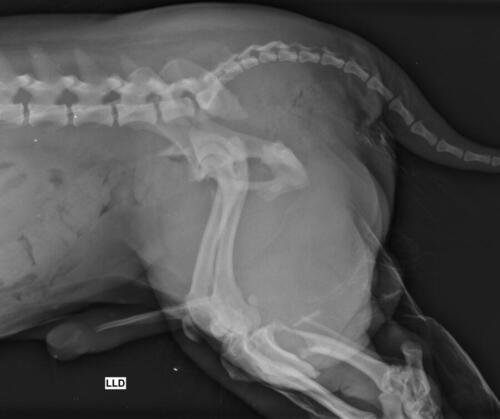

Olá, me chamo Jacqueline sou a mãe do chokito de 4 patas 🐶. No dia 07/02/2025 chokito foi atropelado em frente a minha casa, onde resultou no quadril dele quebrado e a patinha direita traseira quebrada tbm (a tíbia). Quem atropelou ele não parou pra prestar socorro a ele, e mto menos quis saber oque havia acontecido. Chokito foi atropelado na frente dos meus filhos, duas crianças um autista de 5 anos e uma criança de 3 anos, onde o acidente poderia ter acontecido com um deles, mas graças a Deus, Deus livrou eles, mas infelizmente o chokito não. Desde o dia 07 o chokito sofre de fortes dores constantes, onde ele não consegue se movimentar, para se alimentar ele precisa de ajuda, pra beber água, está com dificuldade em evacuar por conta das fortes dores que ele vem sentindo. Preciso de ajuda pra dar uma qualidade de vida pro chokito voltar a andar e parar de sentir dores constantes. A cirurgia ficou em torno de R$5,500 reais, um valor ao qual eu não consigo pagar, tudo tem sido mto caro, tenho gastado com remédios, Raio x, veterinário, já a cirurgia está mto a cima do que eu poderia pagar pra ajudar ele. Chokito é um cachorro que já foi abandonado e maltratado, pegamos amor e cuidamos dele, meus filhos sofrem por não poder brincar com o cachorro deles e ver o cachorro sempre gritando de dor é uma tristeza para todos nós. Por isso preciso de ajuda pra custear essa cirurgia que ele tanto precisa. Por favor quem puder me ajudar de alguma forma pra que ele volte a andar e parar de sofrer. Estou com meu coração dilacerado vendo ele sofrer sem poder fazer mais do que eu já estou fazendo que é cuidar dele. Cada dia que passa é mais tempo que ele passa sofrendo e agravando a situação que ele se encontra.